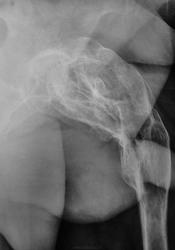

Консолидированный перелом шейки и диафиза бедренной кости... Укорочение конечности?

По поводу чего делались снимки? Возможно, какая-нибудь дисплазия. Больно много наворочено.

Да, укорочение конечности есть.

Наверно, Реклингхаузена? Уточнить только - гиперпаратироз или нейрофиброматоз.